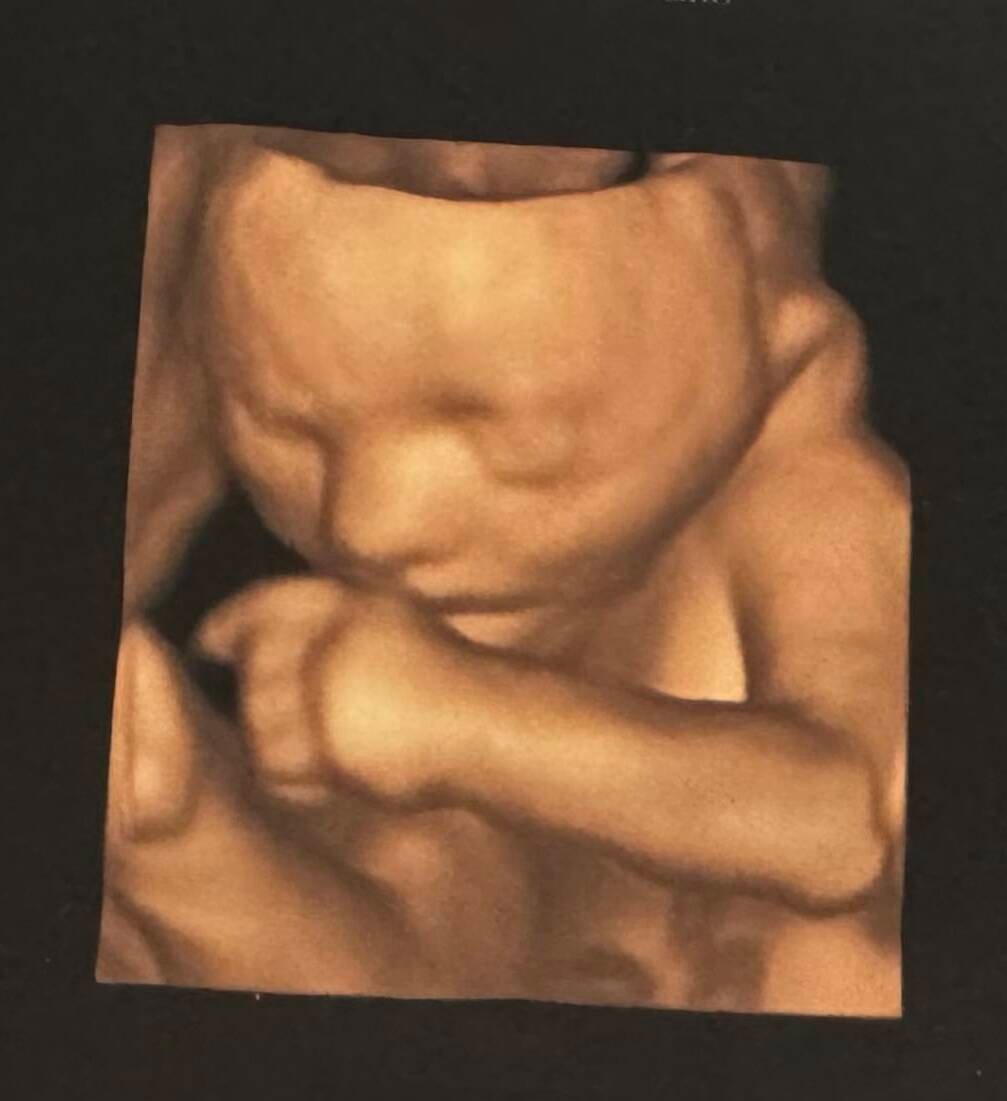

3D Ultrason (Üç Boyutlu Ultrason)

3D ultrason, bebeğin üç boyutlu, hacimsel görüntüsünü sunar. Bu yöntemle bebeğin:

- Yüz hatları

- Burun, dudak, çene yapısı

- El ve ayakları

- Vücut konturları

çok daha net ve gerçekçi şekilde görüntülenebilir.

3D ultrason, özellikle yüz ve dış anatomik yapıların değerlendirilmesinde avantaj sağlar. Aynı zamanda anne ve baba adayları için bebeği daha yakından görme fırsatı sunarak gebelikle duygusal bağı güçlendirir.